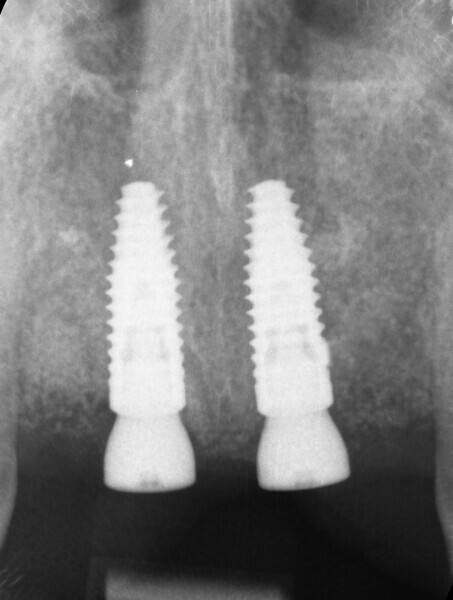

Fig. 12: Intra-oral radiograph of the implants after placement.

After completion of the planning and drilling reconstruction, the surgical guide was 3D-printed with a Stratasys printer using MED610 resin (Stratasys). The two implants (4.1 × 12.0 mm Straumann Bone Level Tapered, Regular CrossFit, SLActive, Roxolid) were then placed utilising the Straumann guided surgery kit for precise guidance. The remaining piece of amalgam in the bone of tooth #21 was carefully removed—only a small piece in the gingiva remained (Fig. 12). The buccal bone was again thickened with EthOss, and the wound was closed with a semi-submerged technique, facilitating proper healing and integration of the implants (Figs. 13a & b).